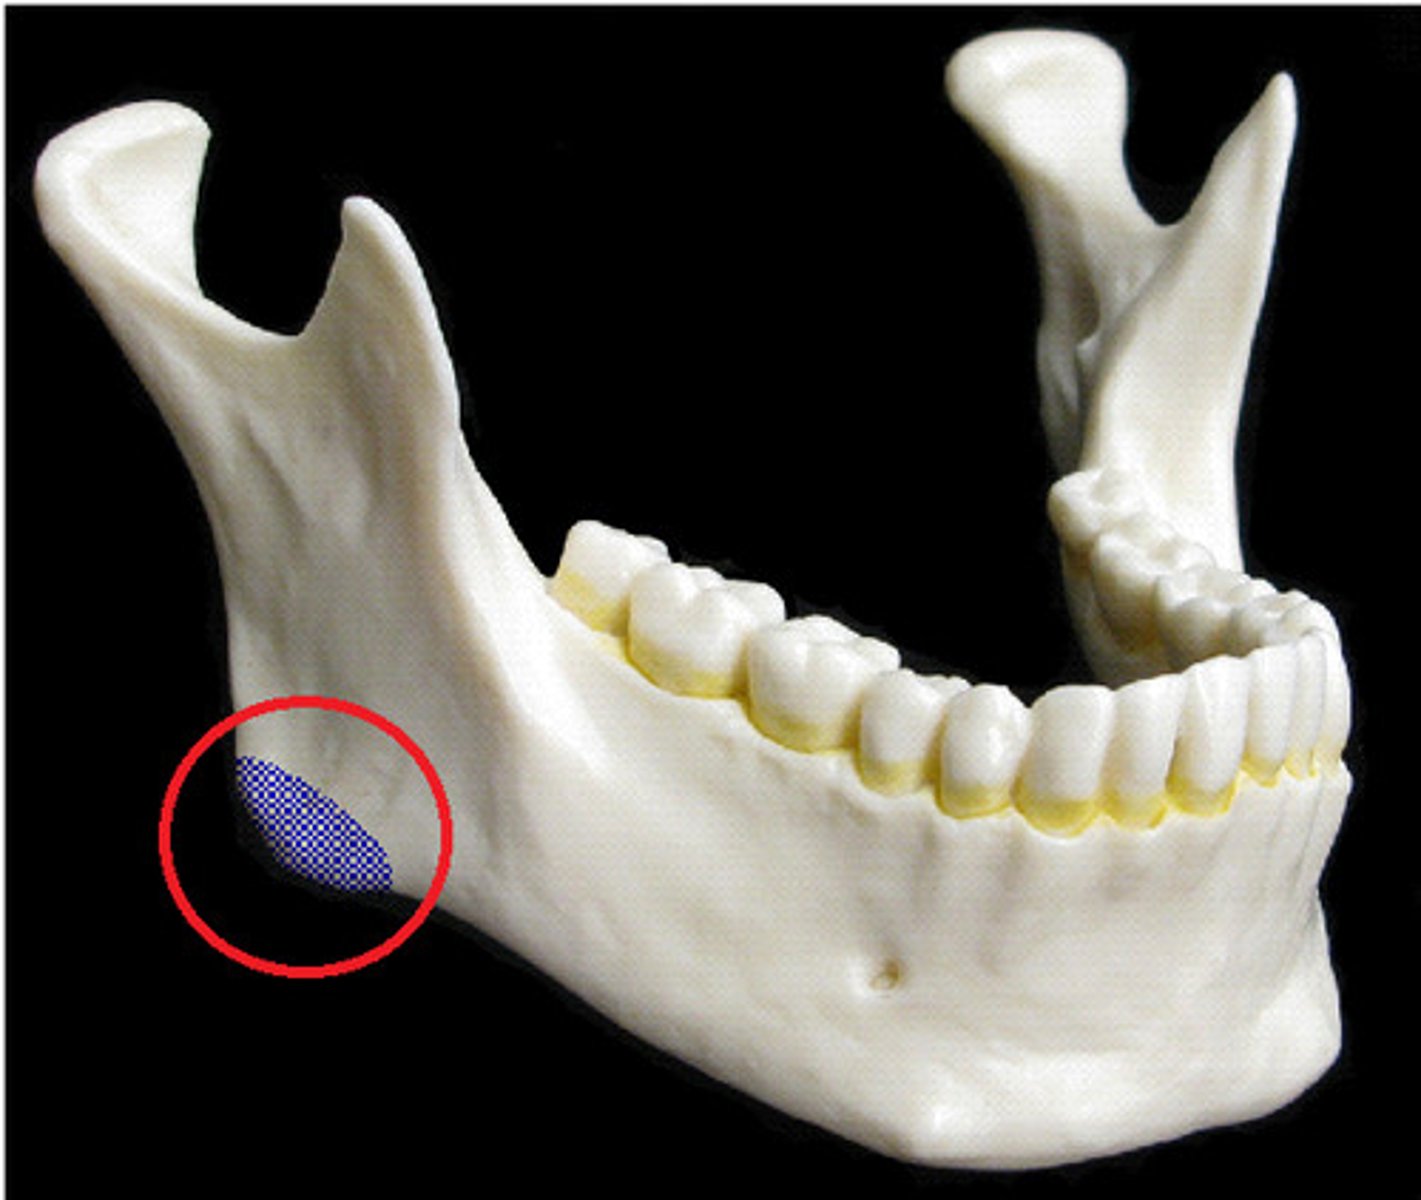

Mental foramen

Name this opening.

Mandibular foramen

Name this bony landmark.

Mandibular foramen

Allows passage of the third branch of the trigeminal nerve (V) on mandible, conveys sensation from the teeth and gums of the mandible

Third division nerve block

Mandibular teeth and gums can be desensitized by an injection of anesthetic near the mandibular foramen